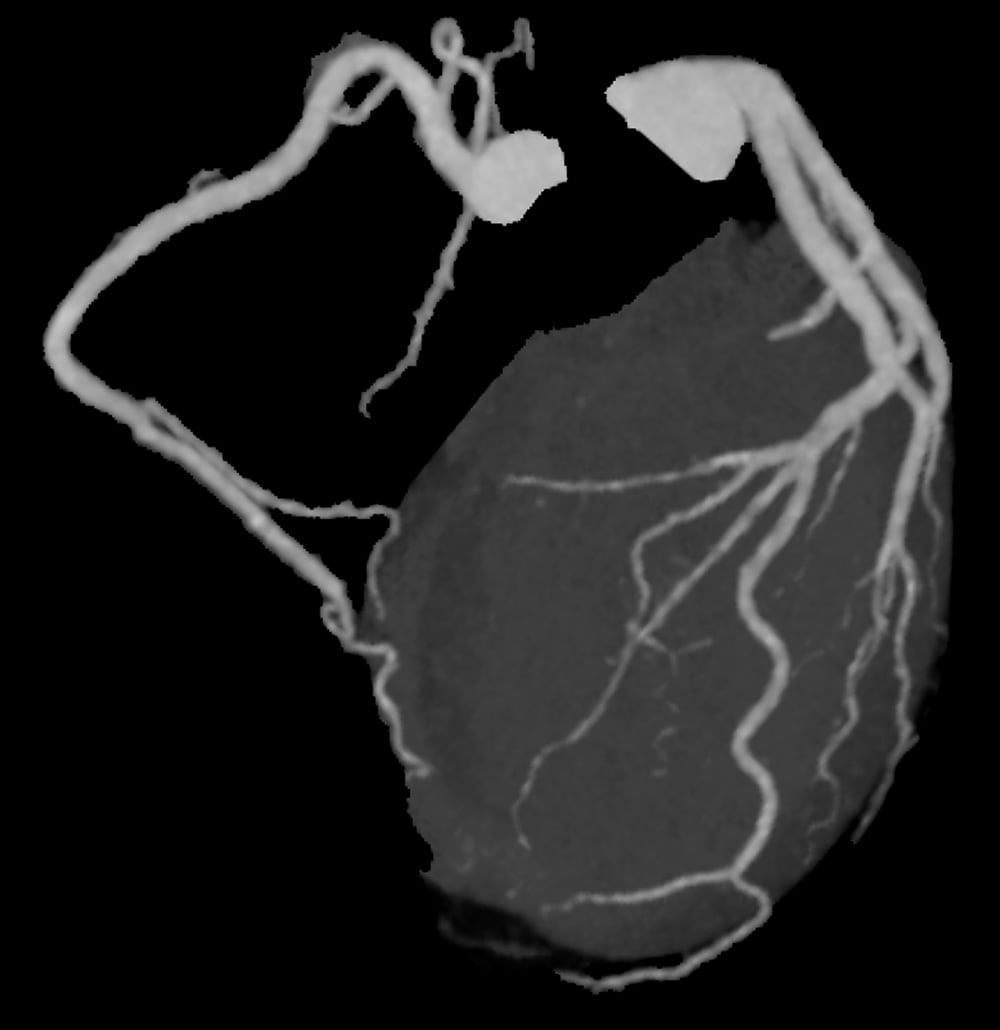

図2.心臓CT 冠動脈Angiographic view

冠動脈にはプラークや狭窄は認められなかった。